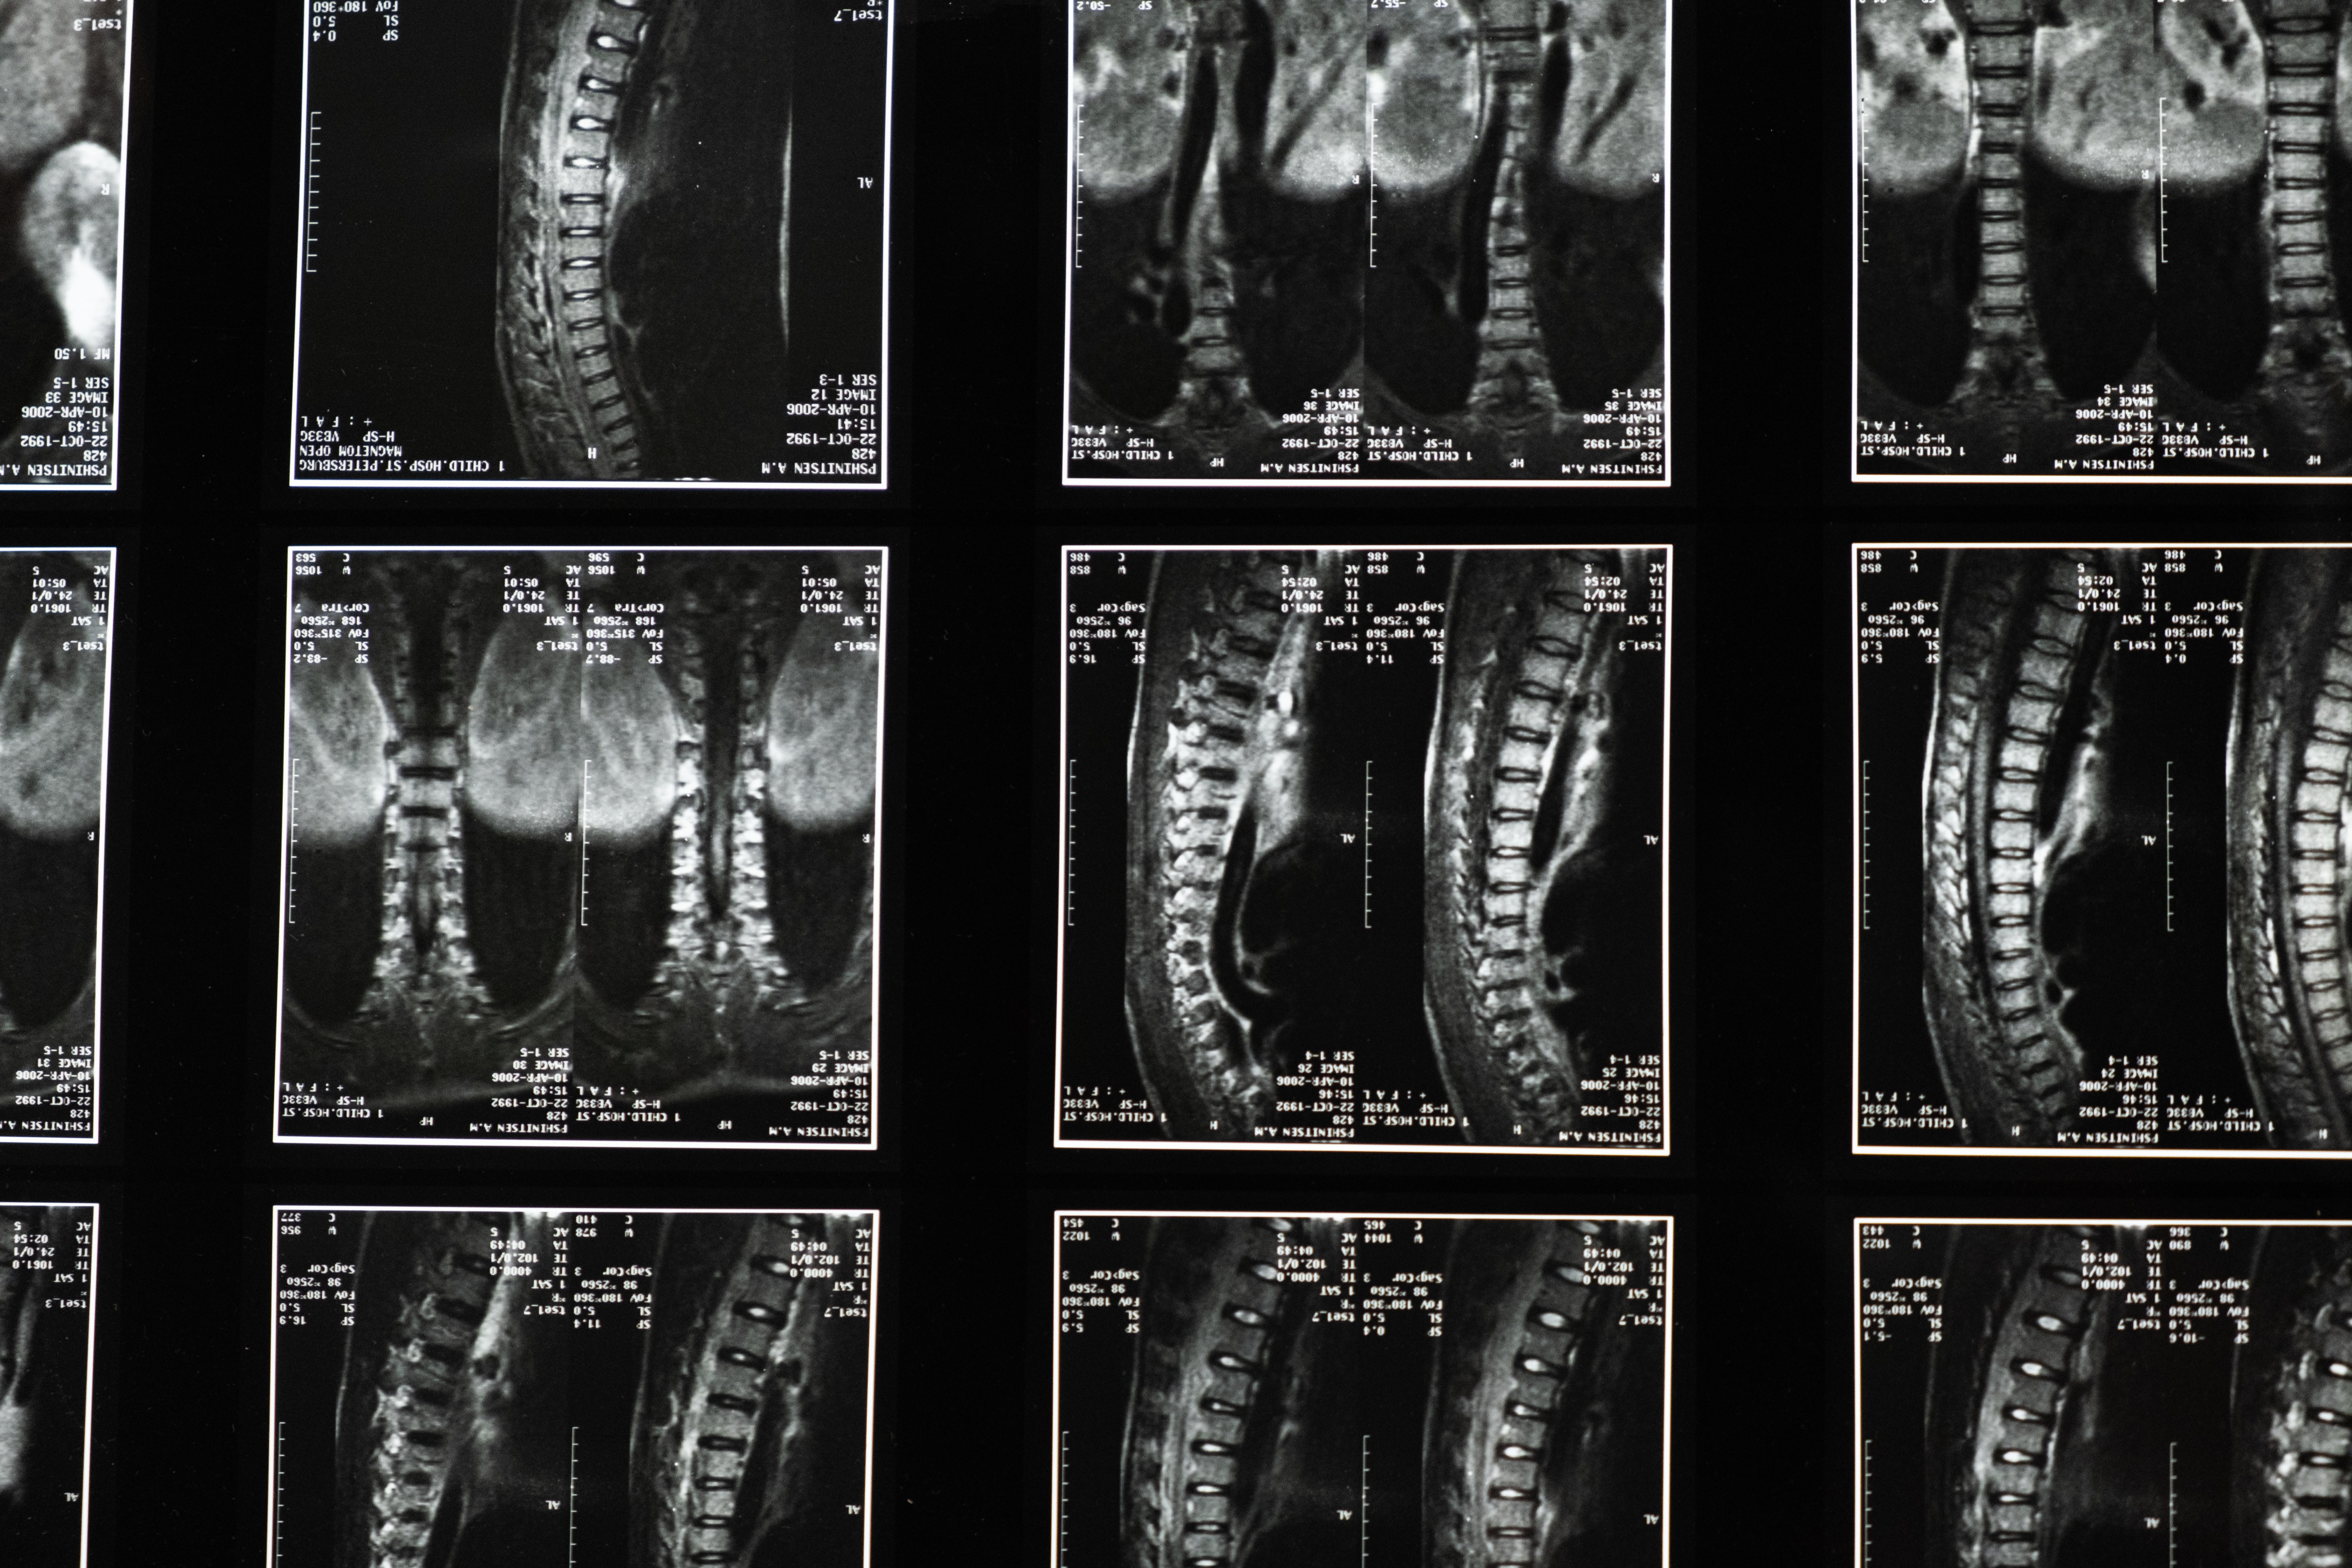

Në eksperimentin e tyre të fundit, shkencëtarët përdorën analiza të avancuara gjenetike për të identifikuar grupet e qelizave nervore jetike për ecjen pas një dëmtimi të pjesshëm të palcës kurrizore. Gjetjet e tyre të mëparshme zbuluan se rigjenerimi i aksonit përgjatë dëmtimit nuk ndihmoi në rikuperim.

Në të kundërt, kur sinjalet kimike u përdorën për të drejtuar aksonët rigjenerues drejt objektivit të tyre origjinal në palcën kurrizore lumbare, përmirësimet në aftësitë e ecjes ishin të dukshme te minjtë me lëndime të plota të palcës kurrizore.